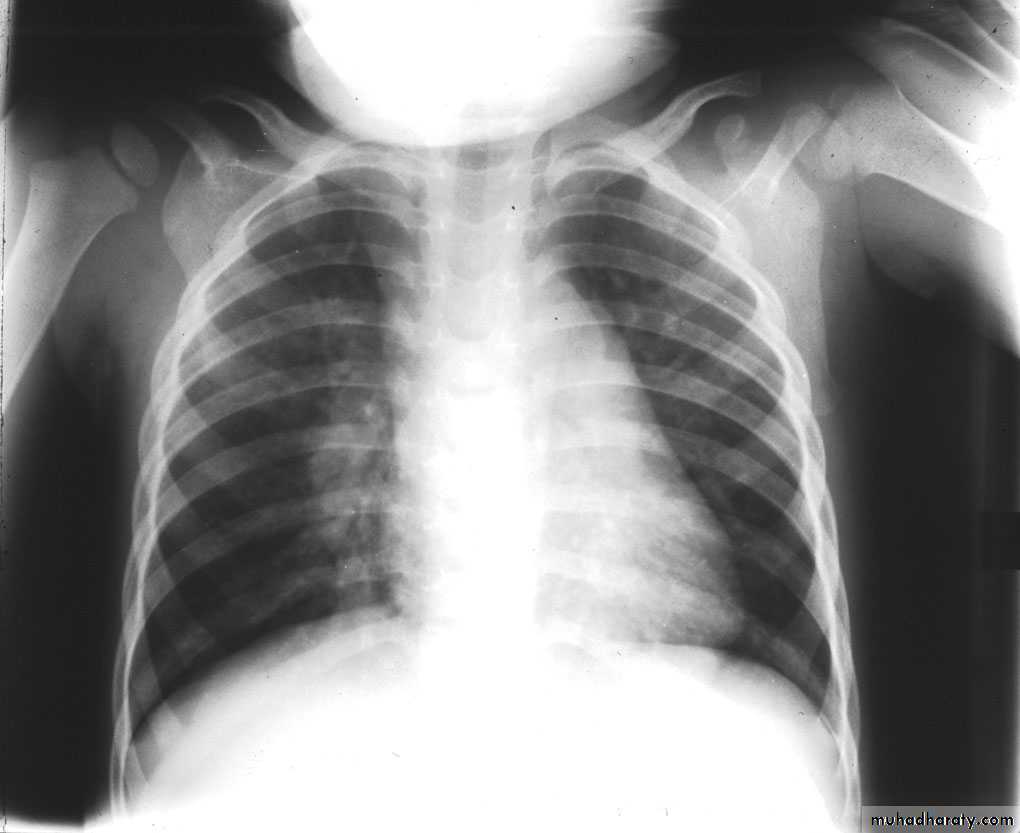

3 month infant presented with cough & dyspnea

Xray shows hyperinflated chest (depresed diaphragm , > 6 ribsMay be bronchiolitis

Hyperinflated chest